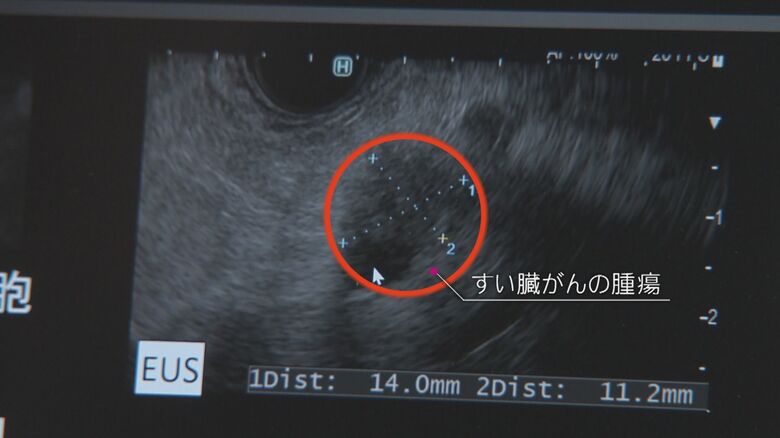

異常に気づかず死亡率高く…“沈黙の臓器”すい臓のガンを早期… ギャラリー 1/13 記事に戻る ニュースONE 2/13 記事に戻る ニュースONE 3/13 記事に戻る ニュースONE 4/13 記事に戻る ニュースONE 5/13 記事に戻る ニュースONE 6/13 記事に戻る ニュースONE 7/13 記事に戻る ニュースONE 8/13 記事に戻る ニュースONE 9/13 記事に戻る ニュースONE 10/13 記事に戻る 11枚目以降の画像を見る 1 2